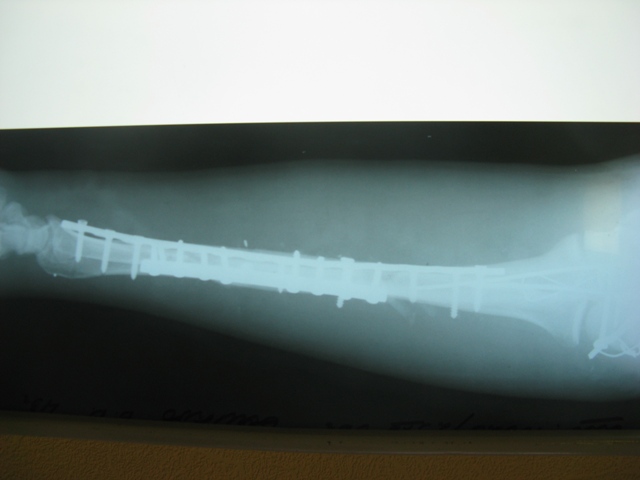

Досылаю остальные снимки, вчера не смог их прикрепить из-за технических причин.

IMG_2649W.jpg

С Новым Годом, уважаемые коллеги!

IMG_2650W.jpg